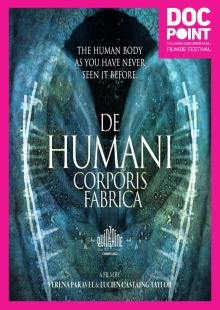

DocPoint 2023: De humani corporis fabrica

Режиссёр Verena Paravel, Lucien Castaing-Taylor

Dokfilmid räägivad tihti sellest, mis inimese sees on, aga harva sellest, mis on PÄRISELT inimese sees. „De humani corporis fabrica“ rändab julgelt koos sondkaameratega inimese sisemusse, et tuua meieni kõik need inimkeha müstilised saladused, mida eelistaksime pigem mitte näha ega kogeda. See pole aga populaarteaduslik film, vaid keha kujutatakse siin kui abstraktsionismi, müstilist lugematute hammasratastega kellavärki, mis tekitab üheaegselt soovi uskuda nii teadust kui ka jumalat.

Olgu, kuidas on, „De humani corporis fabrica“ paneb meid elu kogu selle hapruses armastama ja hin...Показать больше

Dokfilmid räägivad tihti sellest, mis inimese sees on, aga harva sellest, mis on PÄRISELT inimese sees. „De humani corporis fabrica“ rändab julgelt koos sondkaameratega inimese sisemusse, et tuua meieni kõik need inimkeha müstilised saladused, mida eelistaksime pigem mitte näha ega kogeda. See pole aga populaarteaduslik film, vaid keha kujutatakse siin kui abstraktsionismi, müstilist lugematute hammasratastega kellavärki, mis tekitab üheaegselt soovi uskuda nii teadust kui ka jumalat.

Olgu, kuidas on, „De humani corporis fabrica“ paneb meid elu kogu selle hapruses armastama ja hindama. Filmis peitub ka peen kommentaar Prantsuse tervishoiusüsteemi suunal, mis võiks ilmselt aeg-ajalt ka paremini toimida. Lõpustseen New Orderi „Blue Monday“ saatel on valgustuslik. Filmi pealkiri pärineb Andreas Vesaliuse 16. sajandi murranguliselt anatoomiateoselt „De humani corporis fabrica libri septem“ („Inimkeha ehitusest seitsmes raamatus“).

Film mitte igale maitsele, aga kindlasti neile, kes on nõus ilu otsima sealt, kust seda oodata ei oska.